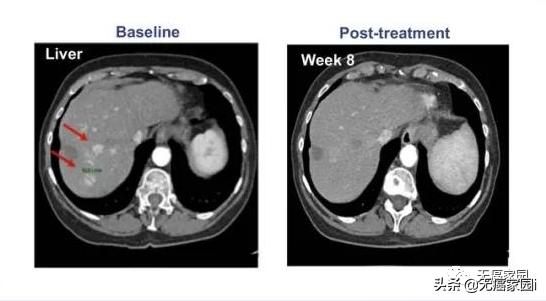

在纳入的患者中, 有一名患者的癌细胞进程出现了完全缓解(CR)的表现,其余参与者的甲胎蛋白(AFP)也都出现了不同程度的下降, 这意味着试验取得了进展,也说明该疗法针对晚期肝癌的治疗是有效果的。

参与的9例患者均接受过手术及常规放化疗,但出现失败或不耐受的现象。在接受最高剂量治疗的4例患者中, 有1例患者获得完全缓解,CT扫描显示,患者体内所有病变都消失了,而且完全缓解后已持续半年以上无任何复发的状态!

其他患者(队列1、队列2)最佳反应是病情稳定。队列2中的1例患者 在治疗1个月后原发病灶体积未缩小,但纵膈淋巴结转移灶体积明显缩小!